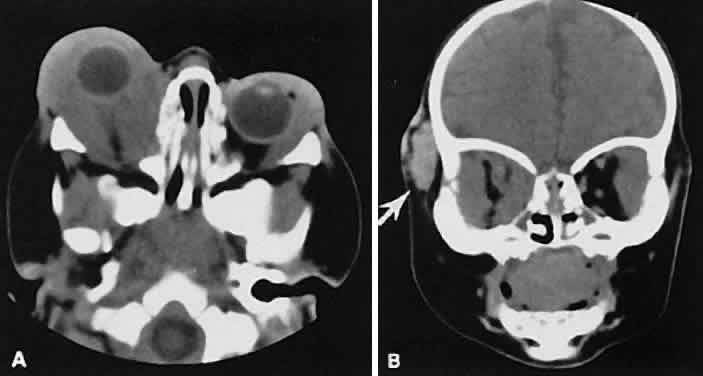

Fig. 6. Nonspecific inflammatory dacryoadenitis. An isodense enlargement of the lacrimal gland is noted on axial (A) and coronal (B) views. Note the similarity to Figure 18.

Fig. 18. Axial (A) and coronal (B) views of lacrimal gland lymphoma. There is homogenous enhancement of the enlarged lacrimal gland. Compared with Fig. 6, there is no difference.